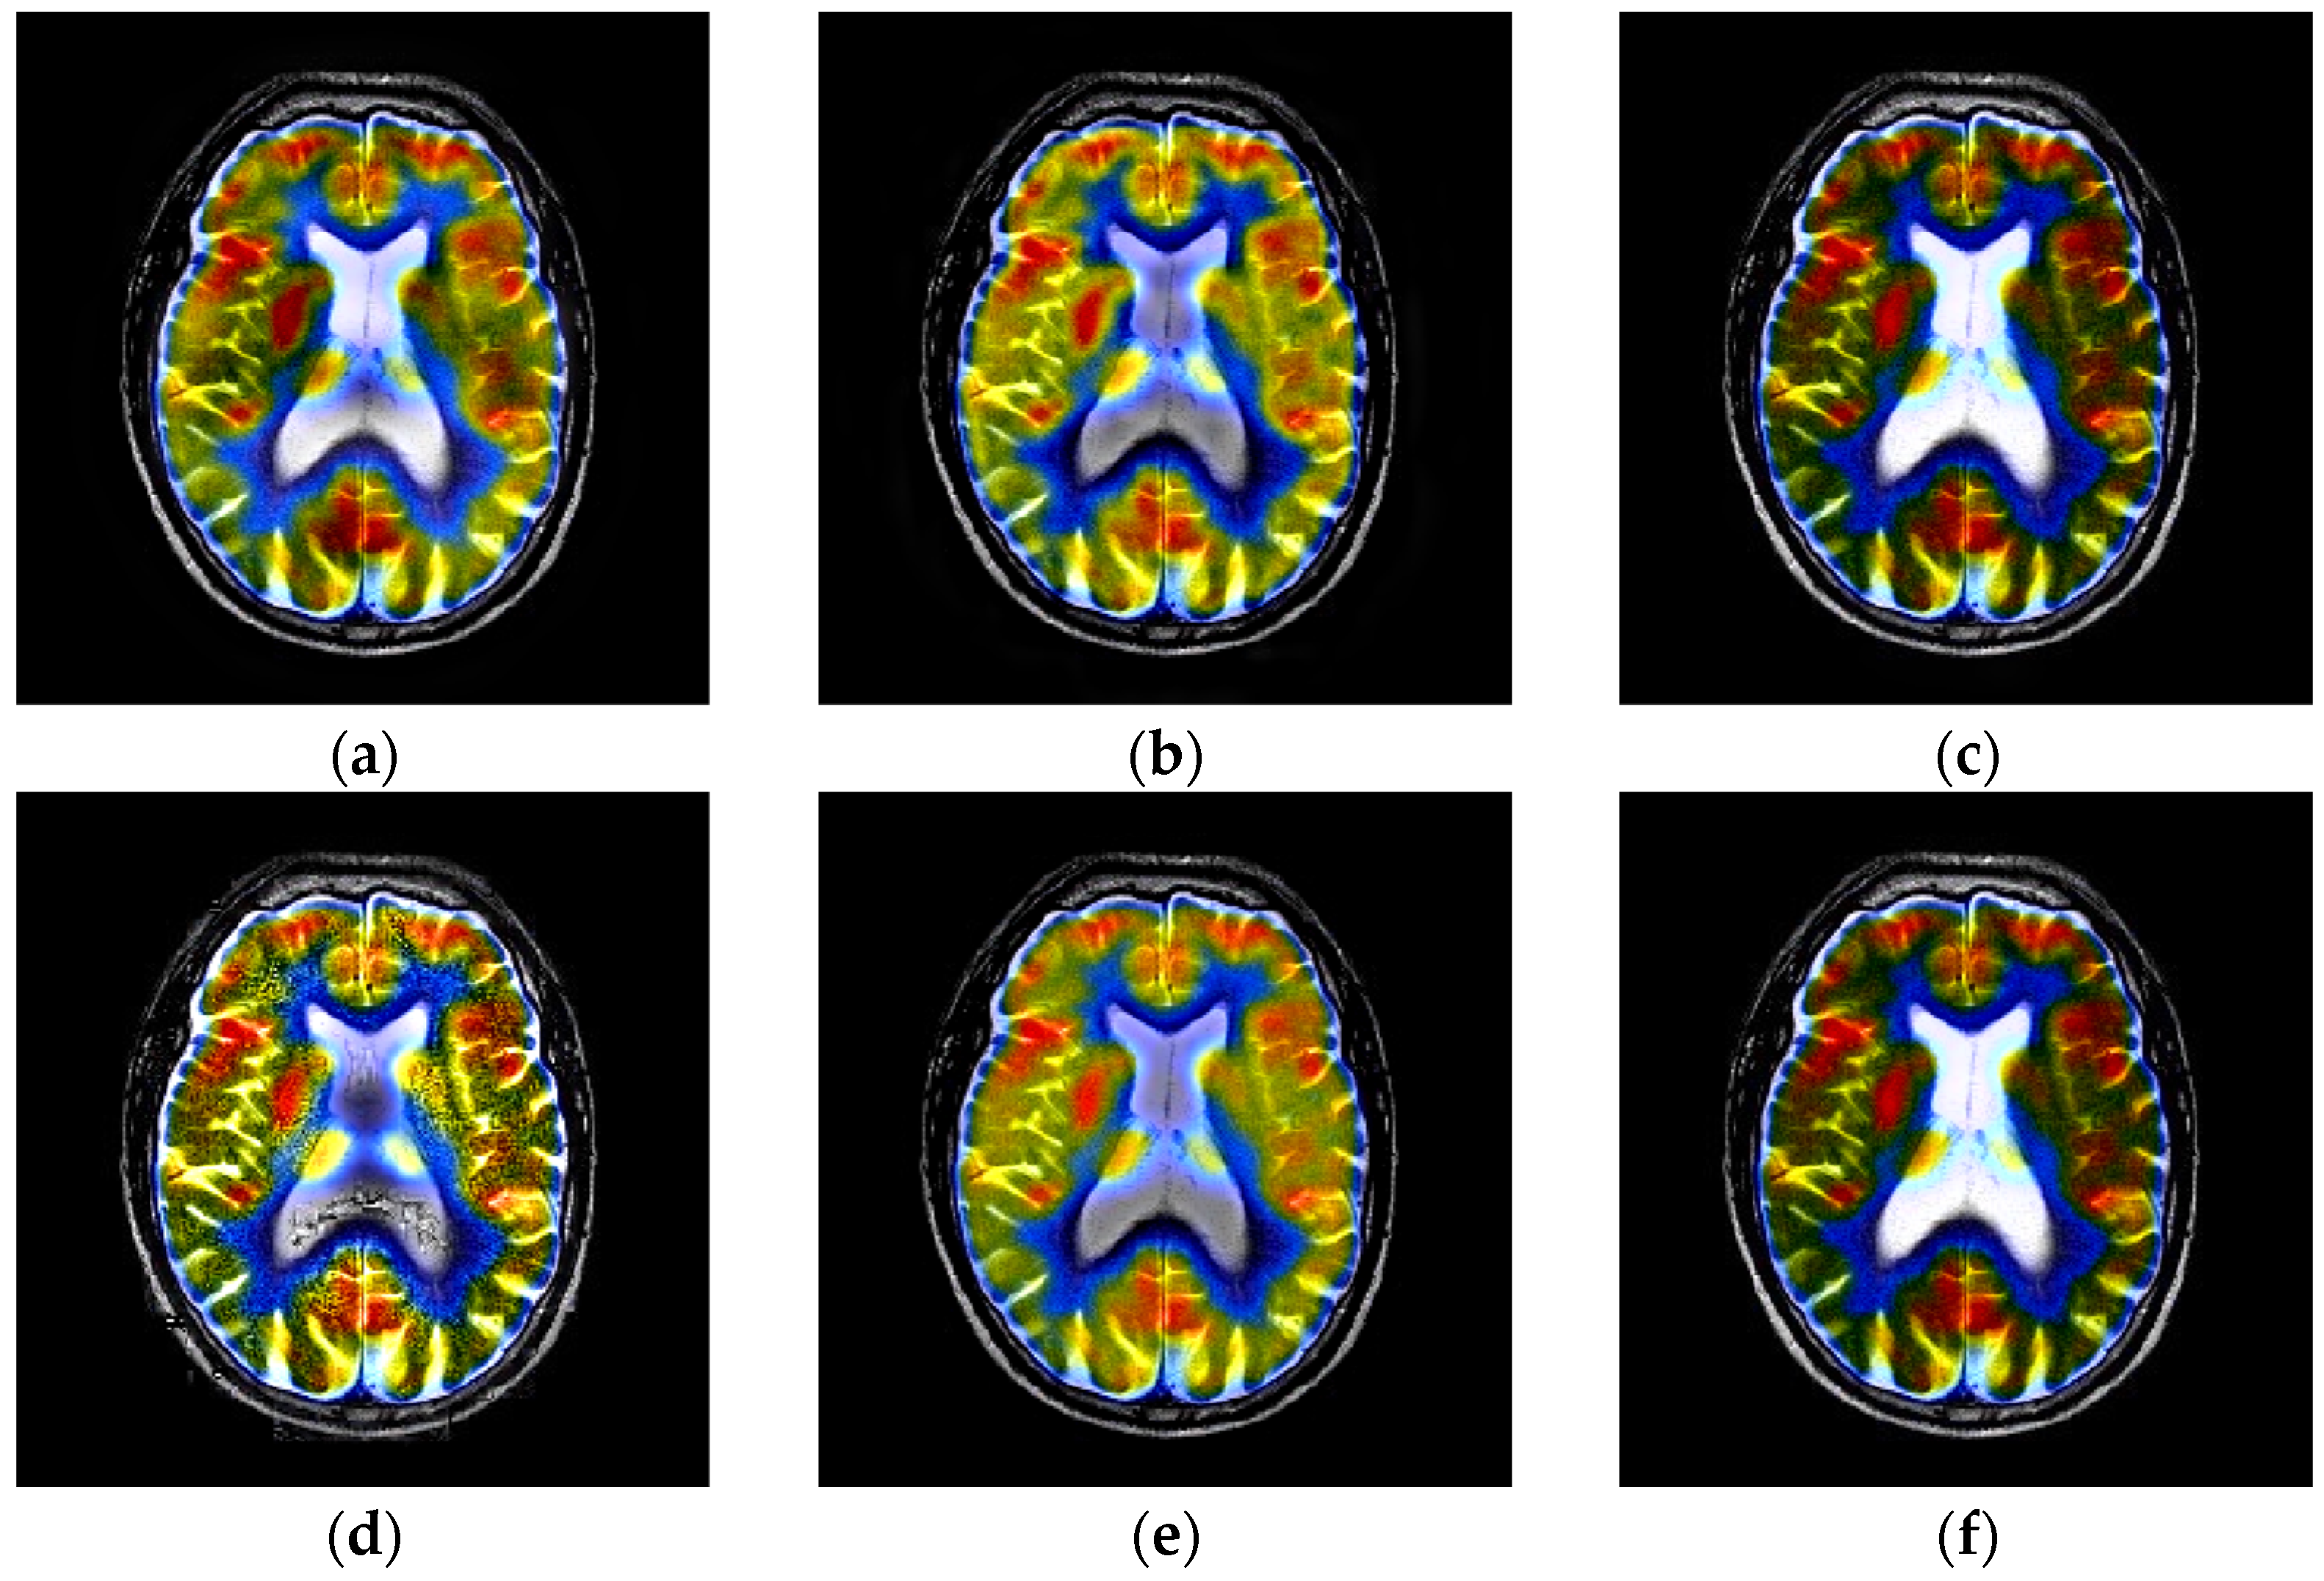

4.2. Comparison of Gray Image Fusion

4.3. Comparison of Anatomical and Functional Image Fusion